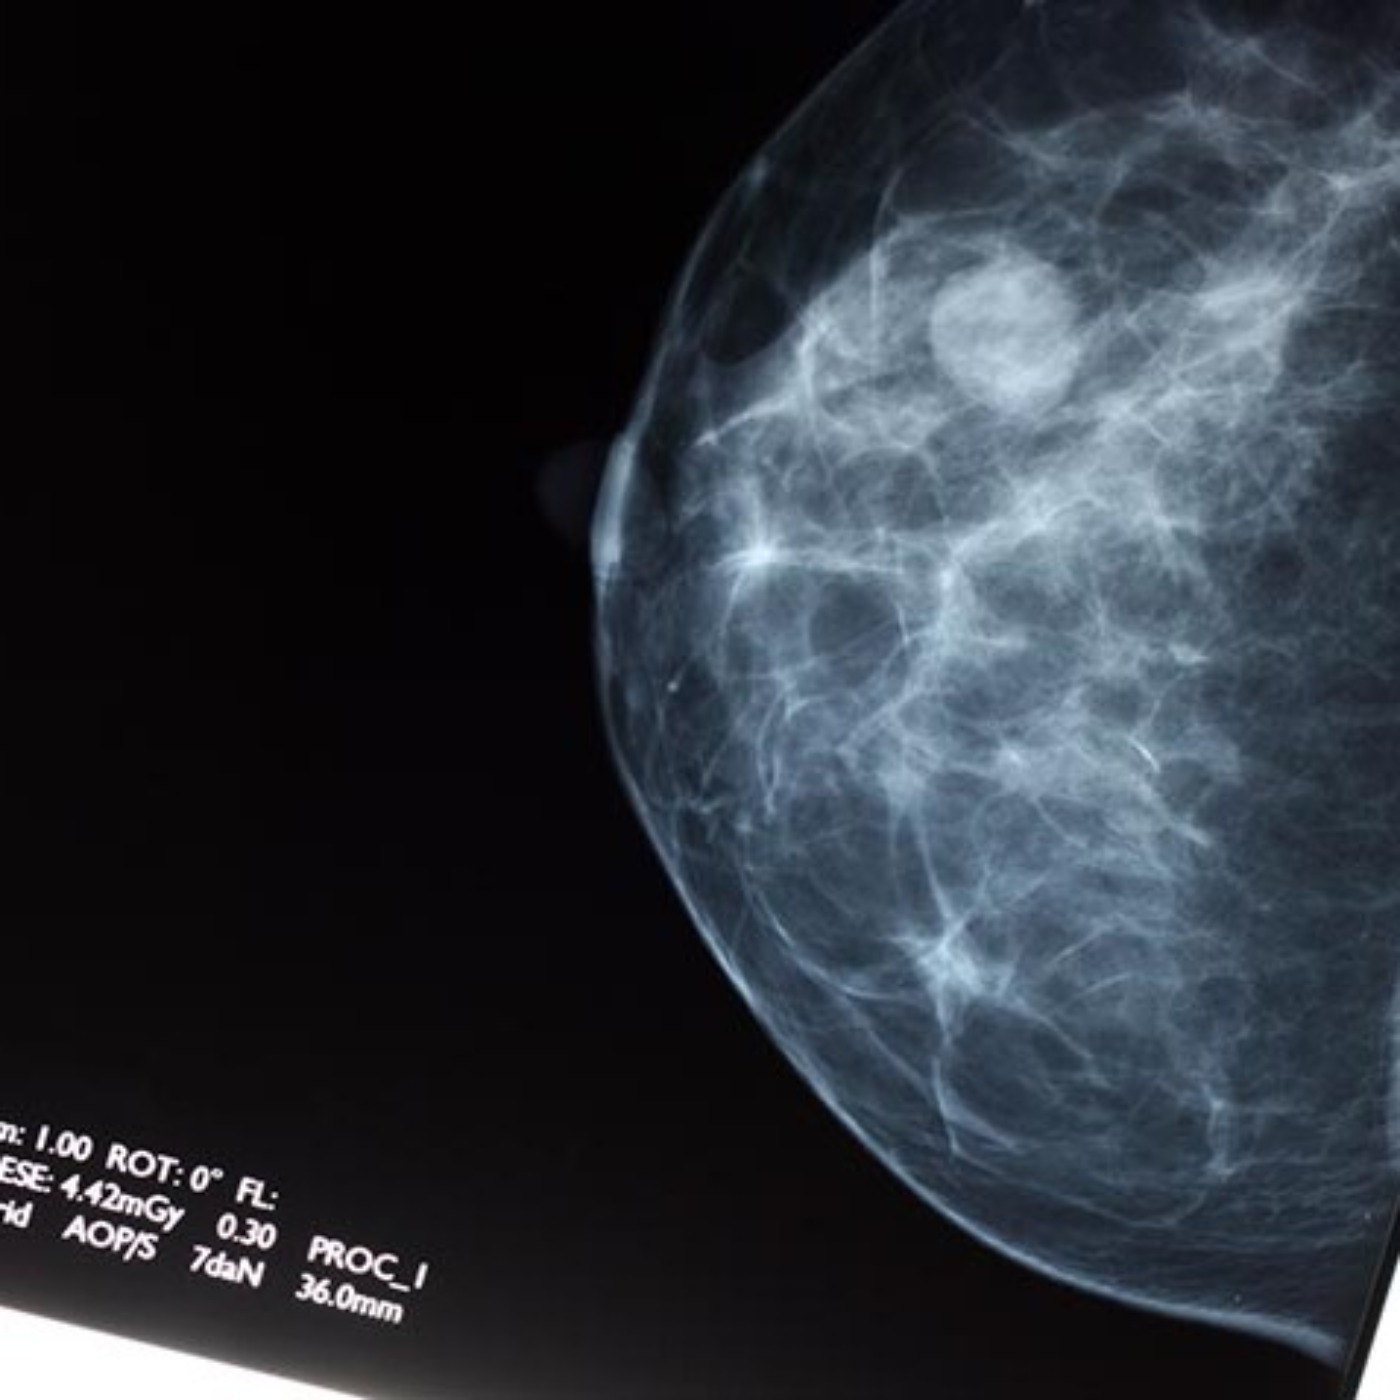

How often should women get a mammogram? A new study makes a case for getting screened every year instead of every other year.

Women diagnosed with breast cancer after receiving yearly mammograms had smaller tumors and less-advanced disease than women who had mammograms every other year, researchers from the University of Michigan Rogel Cancer Center found. For more information about this story visit https://labblog.uofmhealth.org/rounds/annual-over-biennial-mammograms-linked-to-less-advanced-breast-cancer.